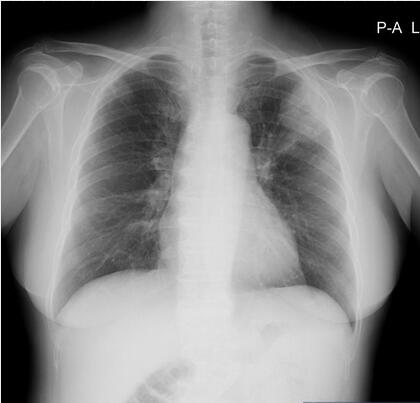

【答案公布】女,56岁,因特发性血小板减少行脾切除术前,胸部X片偶见肺部病灶